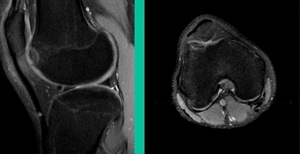

This is an 11-year-old. Left knee lateral knee pain. Effusions, the same type of classic findings (Figure 3)

You look at this one, you say, “what are you going to see when you get in there?” This is one when you get in there, you say, I’m not even sure I’m in the right knee because you almost don’t see it. That happens in patients who were painful, but they don’t look macroscopically unstable. Pediatric orthopedic surgeons tend to drill these. These are the ones that I see as failures. I think when you’re talking about something that’s mechanically unstable, it’s hard to understand why drilling would actually make it work without fixation. Even if it’s microscopically unstable.

The challenge is this. This series of patients were populated by early decisions to treat when patients don’t have symptoms. That’s a problem in my mind. Post-Op, they protect their weight-bearing. That’s actually treatment. These are often smaller lesions of the medial femoral condyle. They do really well. That being said, it’s an option. It’s not my option. My option for someone who’s macroscopically unstable is we use biocomposite screws (Figure 4).